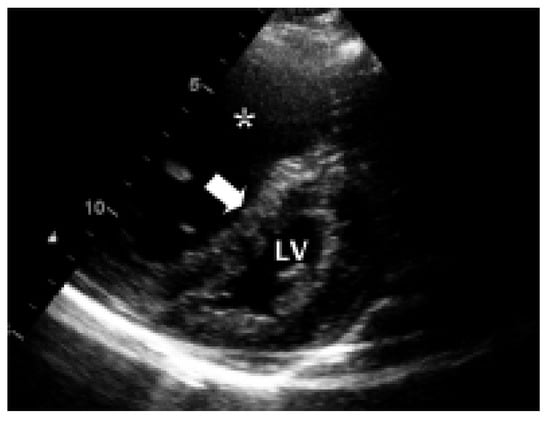

Myocardial Perfusion SPECT Features of Severe Pulmonary Artery Hypertension

Case Report